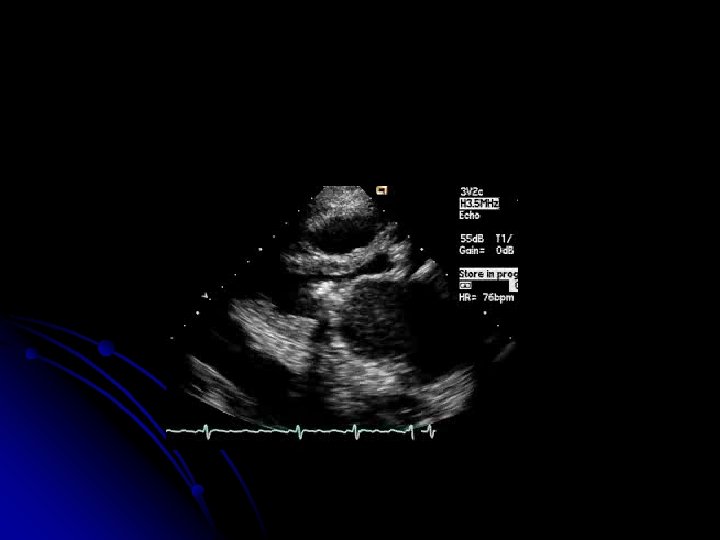

LEFT PARASTERNAL, LONG AXIS VIEW STENOTIC MITRAL VALVE